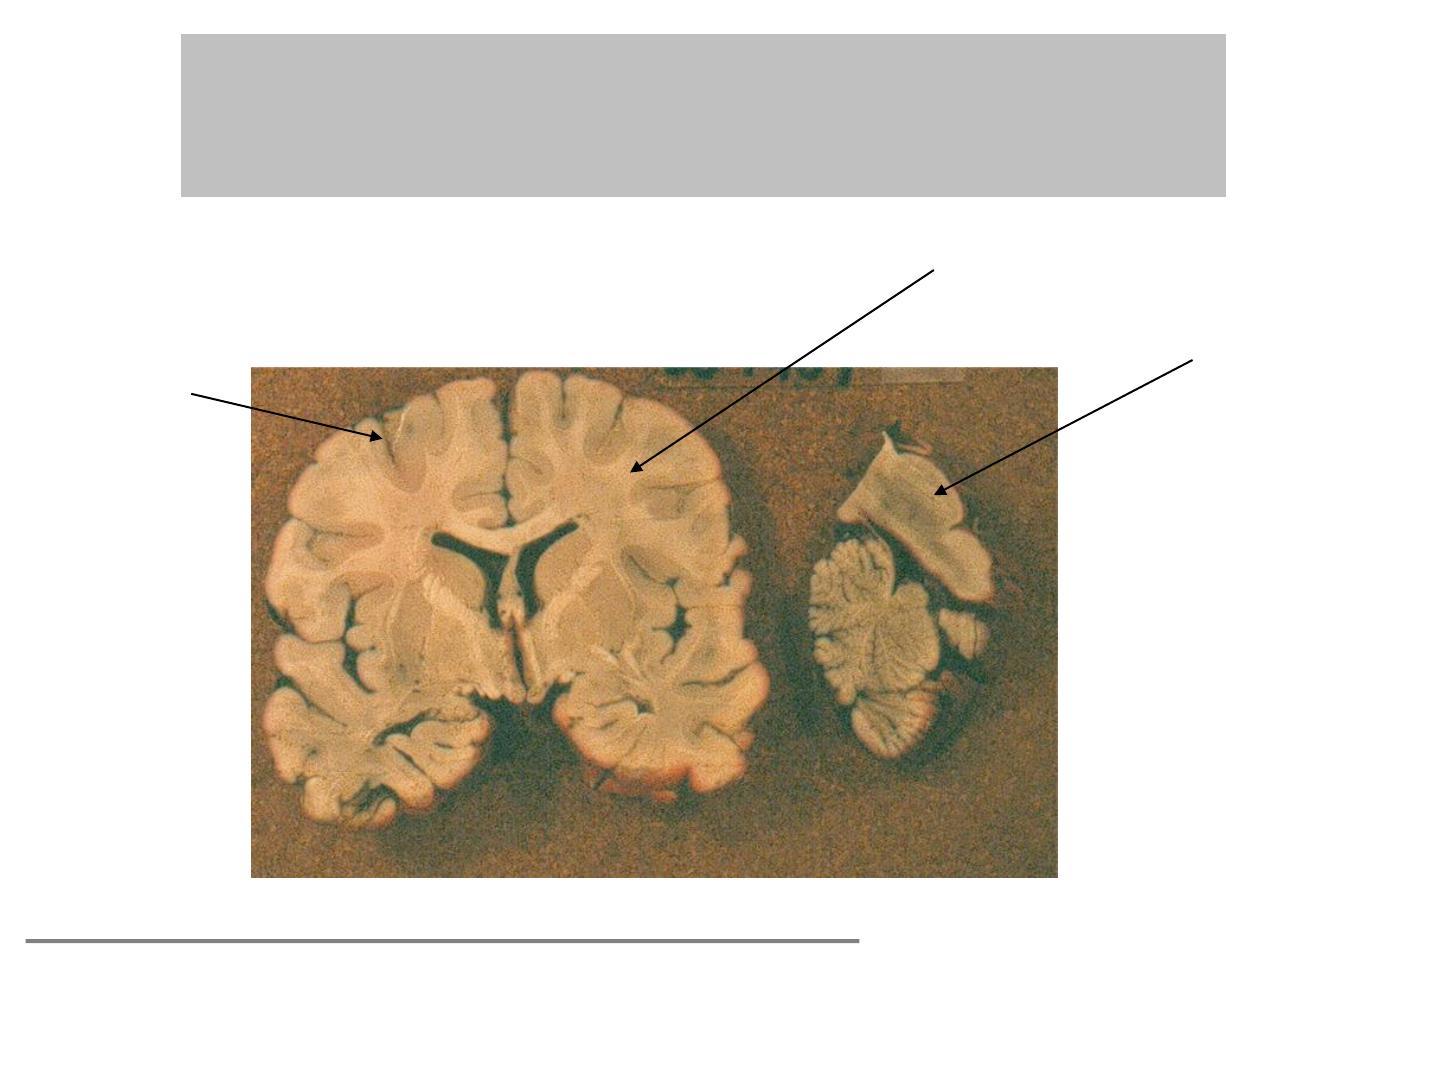

En macroscopie:

Substance grise et Substance blanche

Corps cellulaires

neurones

Axones

Gaine de myéline (lipide)

couleur blanche

Selon les régions du système nerveux:

Proportion et

répartition différente substance grise et substance blanche